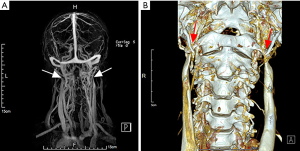

Among the 27 cases, only one patient underwent surgical intervention. This 49-year-old male, who complained of intermittent headaches, persistent head noises and tinnitus for 3 years, was confirmed the diagnosed as severe bilateral IJVS surrounded by abnormally distorted vertebral venous plexuses by CE-MRV in Xuanwu Hospital in November 2017. 3D reconstruction CT maps showed the bilateral IJVS at J3 segments were obviously compressed by the adjacent lateral mass of C1 and styloid process. The styloid processes length was 4.4 cm in left and 4.1 cm in right (Figure 1). The patient underwent bone resection and balloon dilation in left IJV after finished his comprehensively preoperative assessment, as the outflow disorder in left IJV was more severe than that in right. Both the styloid process and the lateral mass of C1 on the left side were resected and the left stenotic IJV was corrected by balloon dilation. The symptoms were relieved immediately after surgery. More importantly, at one-year follow-up post-operation, all symptoms were disappeared and the previous left stenotic IJV had restored normal blood flow and the abnormally tortuous vertebral venous plexus was also decreased in his follow-up CTV maps (Figure 2).